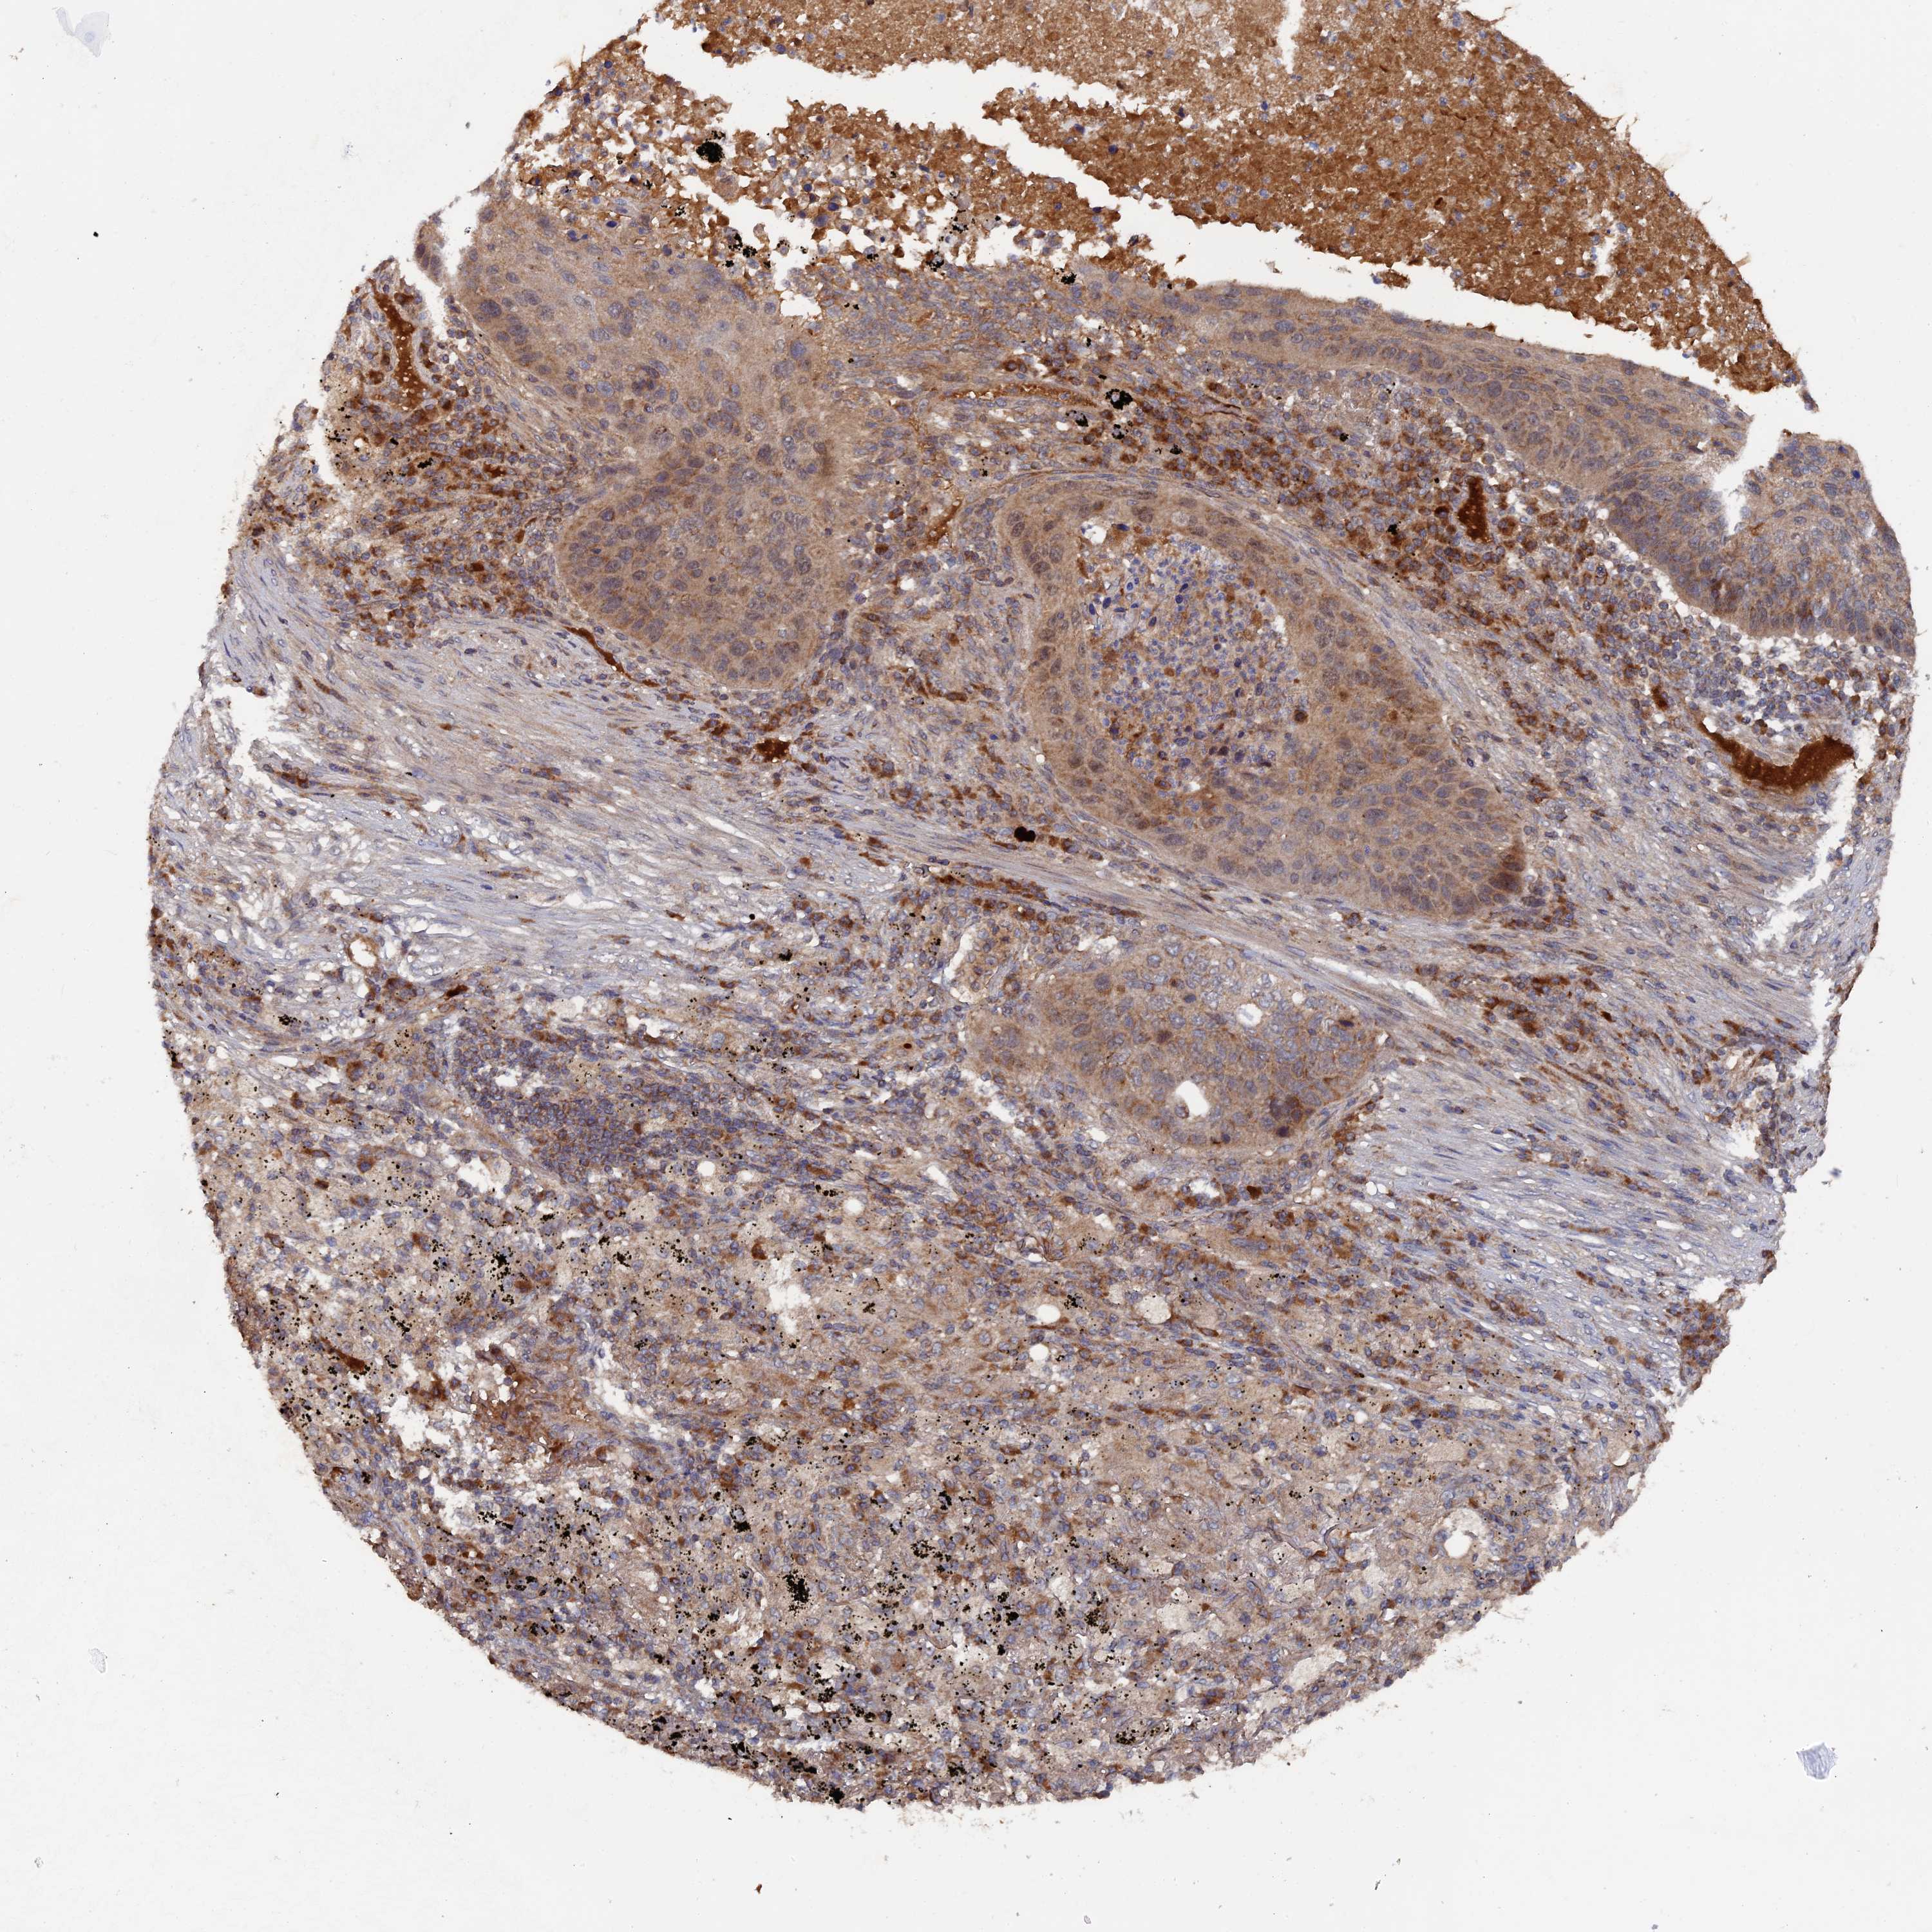

LUNG SQUAMOUS CELL CARCINOMA (TCGA) - Interactive survival scatter ploti

The Survival Scatter plot shows the clinical status (i.e. dead or alive) for all individuals in the patient cohort, based on the same data that underlies the corresponding Kaplan-Meier plots. Patients that are alive at last time for follow-up are shown in blue and patients who have died during the study are shown in red.

The x-axis shows the expression levels (FPKM) of the investigated gene in the tumor tissue at the time of diagnosis. The y-axis shows the follow-up time after diagnosis (years). Both axes are complimented with kernel density curves demonstrating the data density over the axes. The top density plot shows the expression levels (FPKM) distribution among dead (red) and alive patients (blue). The right density plot shows the data density of the survived years of dead patients with high and low expression levels respectively, stratified using the cutoff indicated by the vertical dashed line through the Survival Scatter plot. This cutoff is automatically defined based on the FPKM cutoff that minimizes the p-score. The cutoff can be changed by dragging the vertical line or by entering a cutoff value in the square labeled "Current cut-off".

Under the Survival Scatter plot the p-score landscape (black curve; left axis) is shown together with dead median separation (red curve; right axis). Dead median separation is the difference in median mRNA expression between patients who have died with high and low expression, respectively. It is calculated as follows: median FPKM expression of dead patients with high expression - median FPKM expression of dead patients with low expression. This is intended to aid the user in visually exploring custom cutoffs and the associated p-scores and dead median separation.

Individual patient data is displayed and can be filtered by clicking on one or more of the category buttons on the top of the page. Categories describing expression level and patient information include: high, low, alive, dead, female, male and tumor stages. The scale of the x-axis can be toggled between linear and log-scale by clicking on the "x log" button. Mouse-over function shows TCGA ID, patient information and mRNA expression (FPKM) for each patient.

& Survival analysisi

Kaplan-Meier plots summarize results from analysis of correlation between mRNA expression level and patient survival. Patients were divided based on level of expression into one of the two groups "low" (under cut off) or "high" (over cut off). X-axis shows time for survival (years) and y-axis shows the probability of survival, where 1.0 corresponds to 100 percent.

RAB15 is not prognostic in Lung Squamous Cell Carcinoma (TCGA)

Best expression cut offi

Based on the FPKM value of each gene, patients were classified into two groups and association between prognosis (survival) and gene expression (FPKM) was examined. The best expression cut-off refers the FPKM value that yields maximal difference with regard to survival between the two groups at the lowest log-rank P-value. Best expression cut-off was selected based on survival analysis .

When clicking on this number, the vertical dashed line indicating cut-off, the interactive survival plot, and the Kaplan-Meier curve will be adjusted to show results based on the best expression cut-off.

: 10.76

P scorei

Log-rank P value for Kaplan-Meier plot showing results from analysis of correlation between mRNA expression level and patient survival.

N/A

5-year survival highi

5-year survival for patients with higher expression than the expression cutoff.

For melanoma and glioma, 3-year survival is shown.

5-year survival lowi

5-year survival for patients with lower expression than the expression cutoff.

TCGA RNA samplesi

RNA-seq data is reported as average FPKM (number Fragments Per Kilobase of exon per Million reads), generated by the The Cancer Genome Atlas (TCGA) .

Normal distribution across the dataset is visualized with box plots, shown as median and 25th and 75th percentiles. Points are displayed as outliers if they are above or below 1.5 times the interquartile range. FPKM values of the individual samples are presented next to the box plot.

Average pTPM 10.8

Number of samples 489